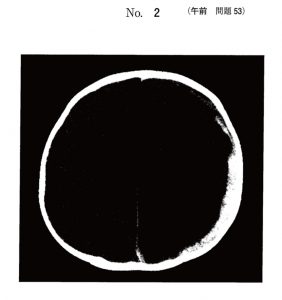

問題53

Aちゃん(生後4か月、女児)は、嘔吐とけいれんのため病院を受診した。受診時、Aちゃんは傾眠状態で、顔色不良と眼球上転がみられたため入院となった。受診時の体温は36.8℃であった。四肢は硬直し、数か所の内出血斑があった。大泉門は平坦であったが、次第に膨降を認めるようになった。

このときの頭部CTを以下に示す。Aちゃんの所見として考えられるのはどれか。

1.急性脳症(acute encephalopathy)

2.てんかん(epilepsy)

3.硬膜下血腫(Subdural hematoma)

4.細菌性髄膜炎(bacterial meningitis)